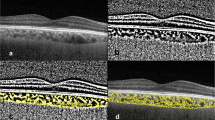

Optical coherence tomography angiography

The retinal microvasculature was assessed using a single OCTA system (Spectralis OCT, Heidelberg Engineering, Heidelberg, Germany). Each patient underwent a 3.0*3.0 mm scan centered on the fovea. The scan was composed of 256 B-scans at a distance of 11 μm each, each B scan included 512 A scans and a single B-scan withan average of 5 frames.The superficial capillary plexus(SCP) and deep capillary plexus (DCP) were automatically segmented, SCP was defined from the inner limiting membrane(ILM) to the inner plexiform layer (IPL), and the DCP was defined from the IPL to the outer plexiform layer(OPL) (Fig. 1). The en-face images of SCP and DCP were exported and then imported into the ImageJ (National Institutes of Health, Bethesda, MD, USA). As previously described,the superficial and deep vessel density were calculated in the 3*3 mm area by the binarized images [13].

OCTA and SD- OCT images of TAO. A OCTA image of SCP in active eye. B OCTA image of DCP in active eye. C SD- OCT image of macular center in active eye. D OCTA image of SCP in inactive eye. E OCTA image of DCP in inactive eye. F SD- OCT image of macular center in inactive eye. SCP:superficial capillary plexus; DCP: deep capillary plexus; OCTA: optical coherence tomography angiography; SD- OCT: spectral- domain optical coherence tomograph

The choroidal vascular parameters were obtained using line scanning mode. The single line pattern scan centered on fovea using the EDI mode of a spectral-domain OCT(SD-OCT) device (Spectralis OCT; Heidelberg Engineering, Germany). The line was 30° in length and was captured in the high-resolution scanning mode. We acquired all OCT scans in the afternoon from 3 to 5 o'clock to control for the diurnal variation of choroidal.

We manually removed the images with unclear choroidal scleral interface so as to maintain the better quality. All images were analyzed using the ImageJ (National Institutes of Health, Bethesda, MD, USA). Firstly, the image was binarized according to Niblack auto-local threshold, then we used the polygon tool to select the total choroidal region from the retinal pigment epithelium to the choroid-scleral junction and added it to the ROI manager. Then we convert the image to RGB format, and the luminal area (LA) was determined using color threshold tool. Finally, the total choroidal area (TCA) and LA were automatically calculated, Choroidal Vascularity Index (CVI) value was determined as the ratio of LA to TCA (Fig. 2).

Measurement technique of choroidal vascularity index (CVI). A The enhanced depth optical coherence tomography(EDI-OCT) images of the subjects. B The binarisation image by Niblack auto local threshold method. C The total choroidal area(TCA) was determined using the region of interest (ROI) manager. D the color threshold tool was used to select the dark pixels, representing the luminal areas(LA).CVI was calculated by dividing LA to TCA

The choroidal thickness (ChT) was considered as the vertical distance from the Bruch membrane to the choroid-scleral junction in the sub-fovea. It was manually measured by two independent examiners.